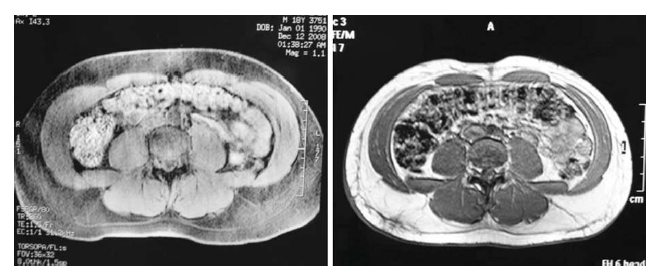

A new liposuction technology for adipocyte lipolysis and uniform three-dimensional tissue heating and contraction is presented. The technology is based on bipolarradiofrequency energy appl...